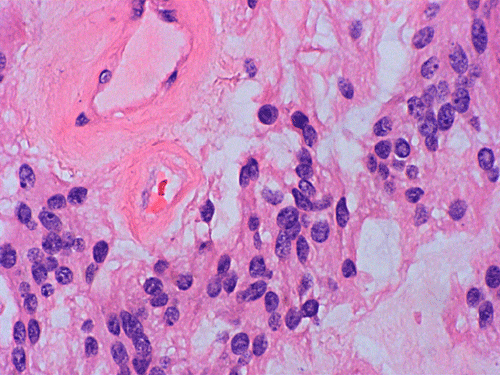

On cytologic preparations, there are clumps of tissue that do not smear out well (Panel A). On higher magnification, these tissue clusters are composed of large blobs of bluish, acellular, mucoid material admixed with cells with relatively uniform, bland nuclei and small amount of cytoplasm (Panel B). In the less tightly packed areas, the long cytoplasmic processes of the cells can be well appreciated (Panel C). These long processes are highly suggestive of a glial neoplasm. On frozen sections, the lesion is composed of multiple blobs of bluish, mucoid material surrounded by tumor cells (Panel D and E). Features of the paraffin sections are not that much different from that of the frozen sections (Panel F G H).

Histopathology: The salient feature of myxopapillary ependymomas is a rich, thin walled micropapillary bundle surrounded by a single of epithelium that varies from low cuboidal to columnar. The cells typically have rounded nuclei with a delicate, rather open chromatin and a moderate amount of amphophilic cytoplasm. The cores of the papillae consist of blood vessels surrounded by a variable amount of mucinous matrix. The amount varies from small to substantial. The vessels are characterized by extensive thickening and hyalinization of the vessel wall. Ins some tumors, there are components with features of conventional ependymomas 24. Mitotic activity is very low or absent 25. Myxopapillary ependymomas usually have sharply defined margins, although nerve roots may be enclosed. A proportion of tumors are surrounded by a condensed connective tissue capsule 11.